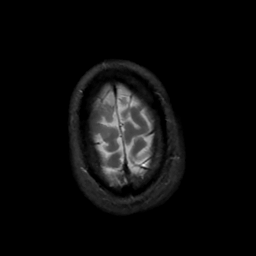

MR Study #5, March 10, 1991 -- Slice #47

[Home][Help][Clinical][Tour 1][Tour 2] Slice 47